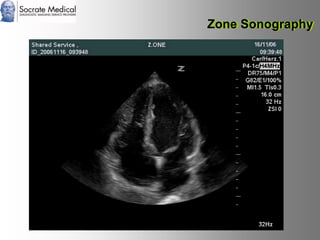

Il documento presenta la tecnologia della zone sonography, che promette una rivoluzione nel campo degli ultrasuoni, superando i limiti dei sistemi tradizionali grazie a metodi di acquisizione dati più veloci e una gestione delle informazioni migliorata. Questa tecnologia consente una maggiore definizione dell'immagine, una riduzione degli artefatti e un'ottimizzazione del processo diagnostico, con vantaggi in termini di tempo e costi. Inoltre, il channel domain processing e la zone speed technology offrono applicazioni avanzate e miglioramenti nella sicurezza diagnostica.